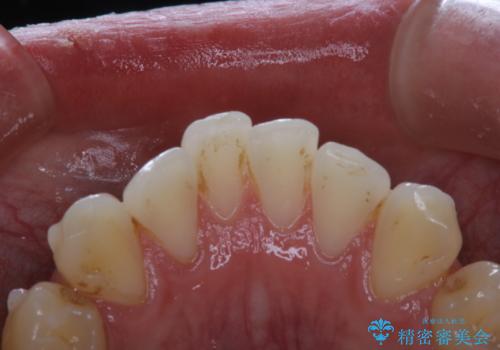

- インビザライン矯正治療中の方です。アタッチメントの周りの汚れが気になるとのことで、PMTC30分コースを行いました。

矯正治療中は虫歯や歯周病リスクが高くなります。

インビザライン矯正治療はマウスピースを長時間使用するため、歯石や汚れなどが付着したままだと、フィットが悪くなったり、口臭が強く出たりする原因につながることもあります。

ぜひ定期的なクリーニングをおすすめします。